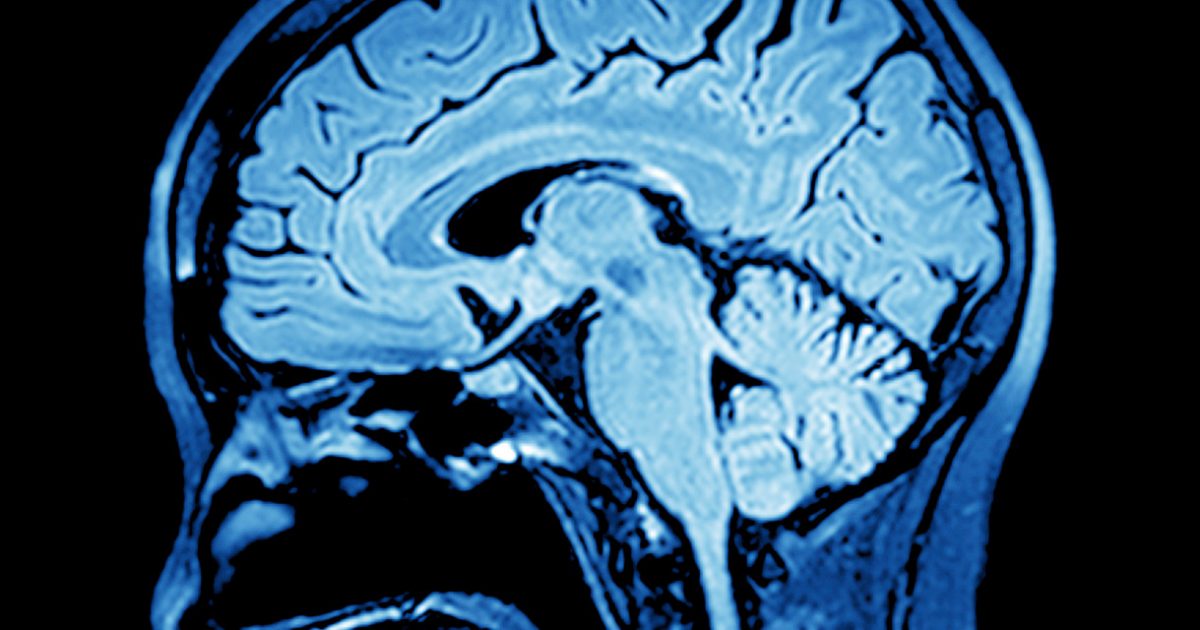

View Can Ms Cause Brain Lesions Pictures. What are brain lesions, and what causes brain lesions? Multiple sclerosis (ms) faqs; the central nervous system and multiple.

Most people with ms know that physically overdoing it can cause ms symptoms to worsen, but mental exertion and emotional upheaval can have the multiple sclerosis lesions are easy to see in white brain matter, but now new types of mri are making it easier to see ms lesions and shrinkage in gray. When trying to diagnose ms, is 10 lesions is a significant number to find? in addition, there is a rough correlation between the number of lesions on the initial mri and the time until the next attack of symptoms. They occur most often from the development of lesions in the area of the brain known as.

Brain lesions may not produce any symptoms at first. The mri showed 10 lesions on my brain. The brain and spinal column often send conflicting signals or no signals at all, which will often cause numbness in the areas of the legs, arms, fingers seizures (epilepsy) are very common in patients with ms. List of 9 disease causes of brain stem lesions, patient stories, diagnostic guides.